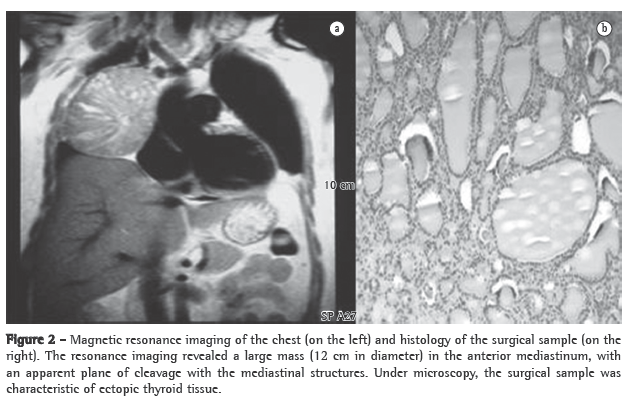

An anteroposterior and lateral right chest X-ray revealed enlargement of the right upper mediastinum.

A CT scan of the chest revealed, in the upper mediastinum, a round, extensive formation (4.5 × 4.3 cm), without signs of infiltration and with well-defined borders, located laterally between the superior vena cava and the right contour of the trachea (Figure 3).

The patients underwent excision of the mediastinal tumor (7 × 5 × 4 cm), and the microscopic report of the surgical sample was consistent with intramediastinal thyroid with a macrofollicular pattern and no cellular atypia.